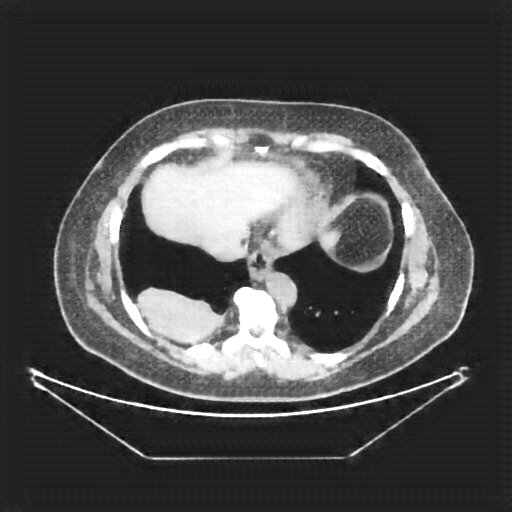

Reconstructed NATIVE CT scan (cycle consistency)

Full window (WL 1023.5, WW 4095 β†’ Low βˆ’1024, High +3071)

Actual HU range: [-1024.0, 631.9]

Lung window (WL -600, WW 1500 β†’ Low βˆ’1350, High +150)

Actual HU range: [-1150.5, 150.0]

Mediastinum window (WL 40, WW 400 β†’ Low βˆ’160, High +240)

Actual HU range: [-160.0, 240.0]